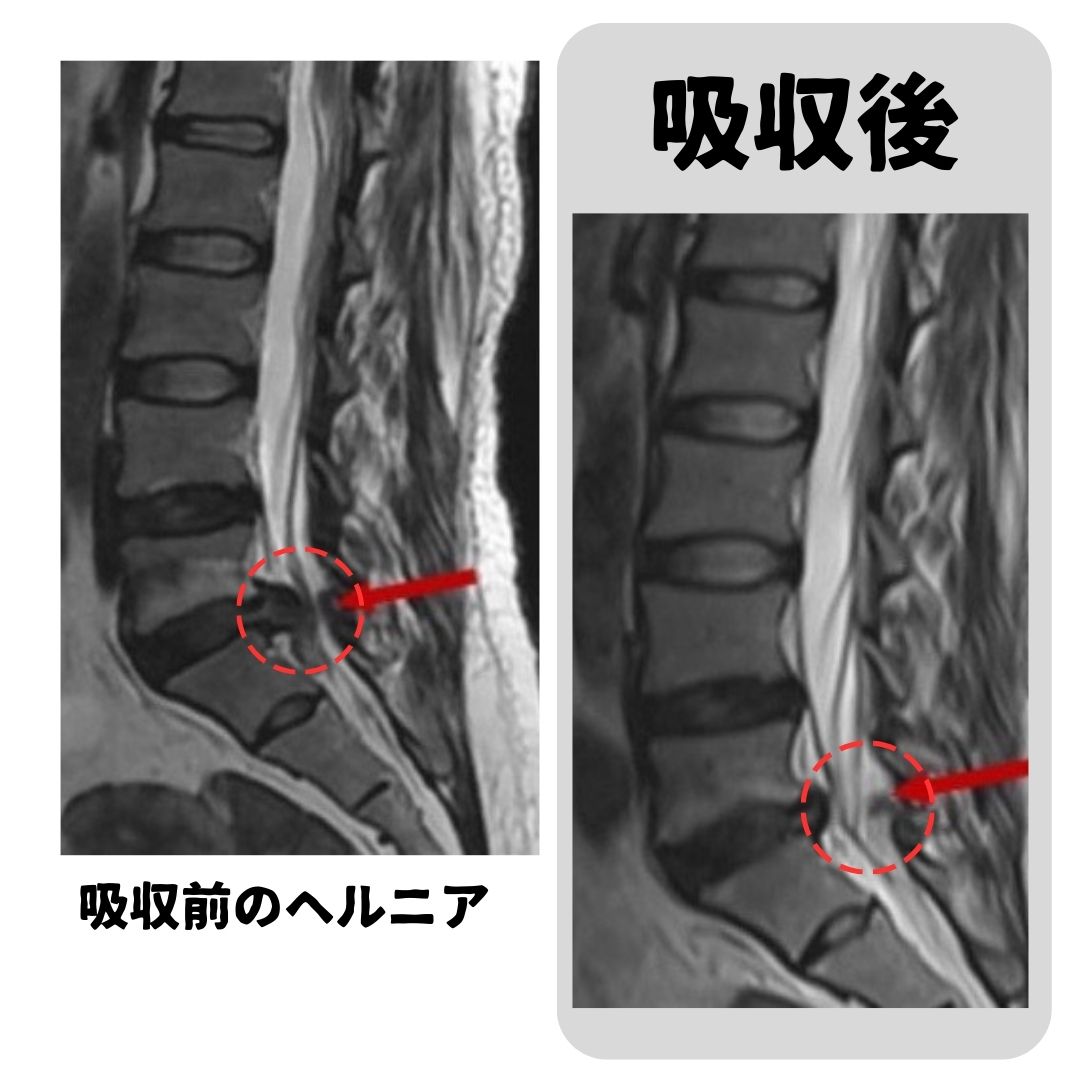

今回は腰椎椎間板ヘルニアについての投稿です。

でも、実はその“ヘルニア”、手術をしなくても改善する可能性があることをご存知ですか?

最新の研究では、なんと約66%が自然に吸収・回復するというデータも。

つまり、3人に2人は自然に回復する可能性があるのです。